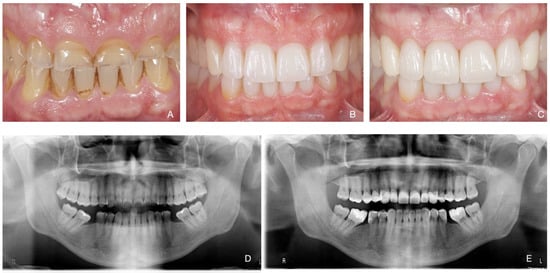

Total Rehabilitation Using Adhesive Dental Restorations in Patients with Severe Tooth Wear: A 5-Year Retrospective Case Series Study

3. Results